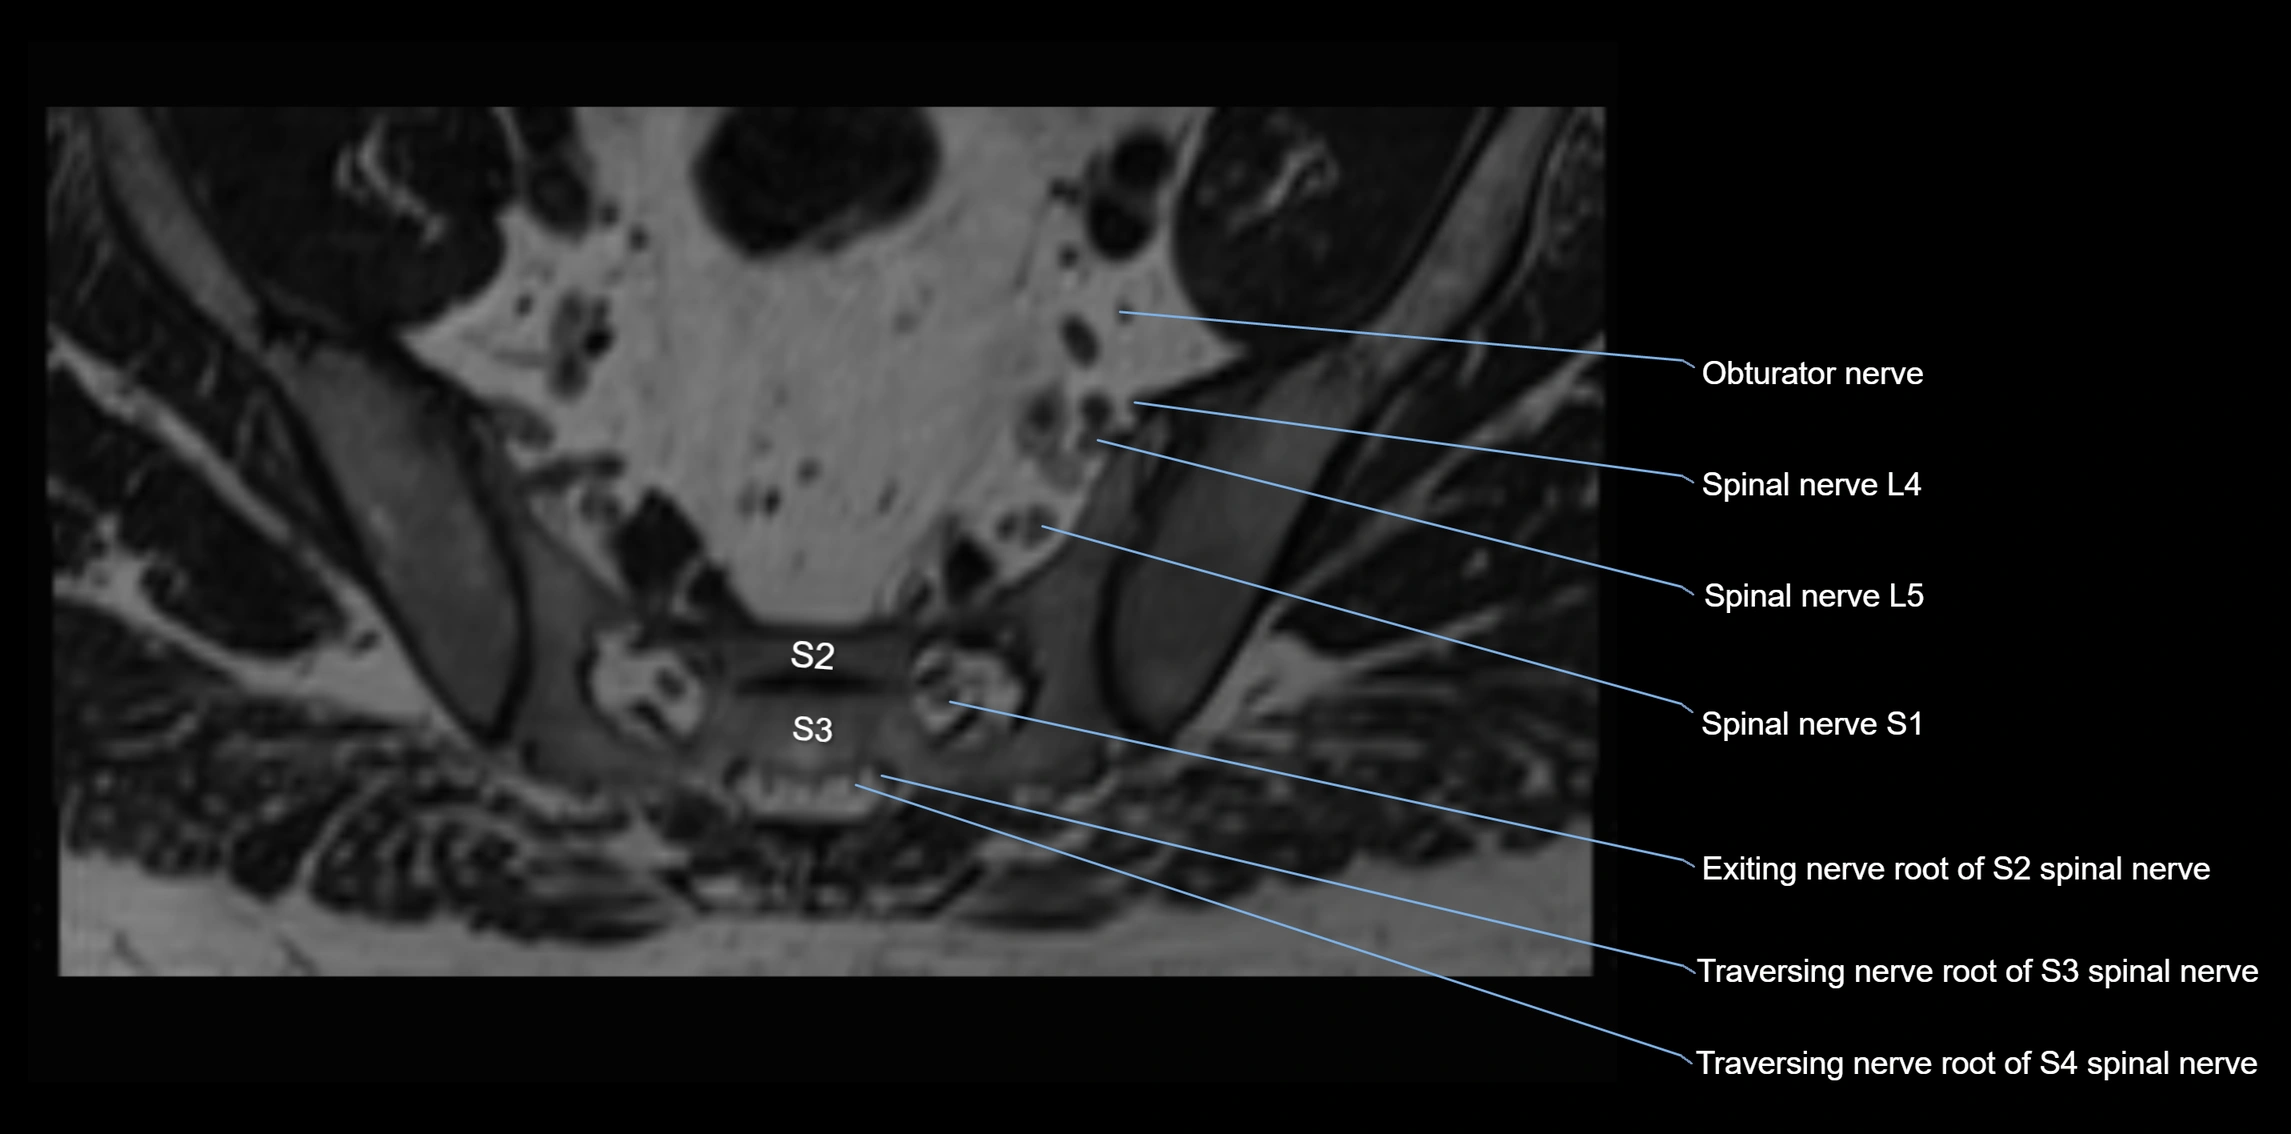

MRI Appearance

T1-weighted images:

• Nerve appears as a very thin low-to-intermediate signal intensity structure

• Surrounded by bright fat, aiding visualization

T2-weighted images:

• Nerve shows intermediate to mildly hyperintense signal compared to muscle

• Pathological involvement appears brighter

STIR (Short Tau Inversion Recovery):

• Normal nerve appears dark

• Inflamed or entrapped nerve appears bright hyperintense

T1 Fat-Sat Post-Contrast:

• Normal nerve enhances minimally

• Pathologic nerve (neuritis, entrapment, tumor infiltration) shows focal or diffuse enhancement

3D T2 SPACE / CISS:

• Nerve appears intermediate to mildly hyperintense compared to muscle

• Surrounded by bright fat or CSF, improving visualization

• Best sequence for mapping small pelvic nerves such as the anococcygeal